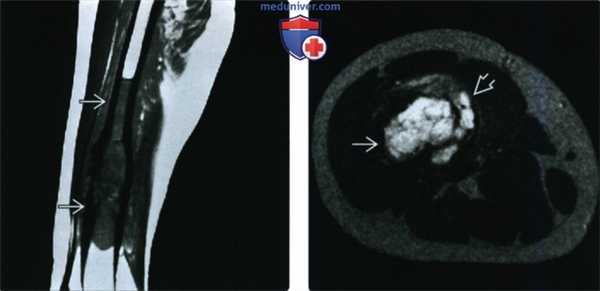

(Слева) МРТ, сагиттальная проекция, режим Т1: у этого же пациента визуализируются признаки диафизарного распространения патологического очага, характеризующегося здесь сигналом средней интенсивности. Патологический процесс охватывает большую, чем можно было предположить по результатам рентгенографии, часть кости.

(Справа) МРТ, аксиальная проекция, режим Т2: у этого же пациента определяется дольчатый высокоинтенсивный очаг в костномозговом канале с медиальным прорывом кортикального слоя и небольшим мягкотканным компонентом. В этом случае ЗФГ специфические диагностические МРТ признаки отсутствуют, но методика позволяет досконально исследовать зону поражения.